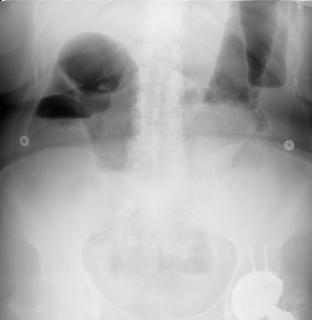

Images hydro-aeriques

d'une occlusion du colon . Ce qui situe

souvent peripherique de l'abdomen et plus hautes que

larges . Cliche ASP expose en debout |